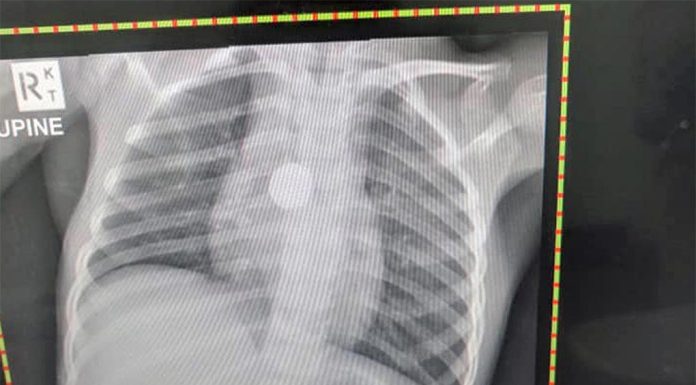

74세미만 관상동맥, 노인은 치매 사망 으뜸

호주인들의 기대수명이 다소 둔화세를 보이고 있다. 지난 30년간 호주인들의 기대수명이 증가물결을 탔으나 지난 6년사이 주춤하는 모양새다. 기대수명이 남녀 모두에서 늘었으나 증가폭이 크게 눈에...